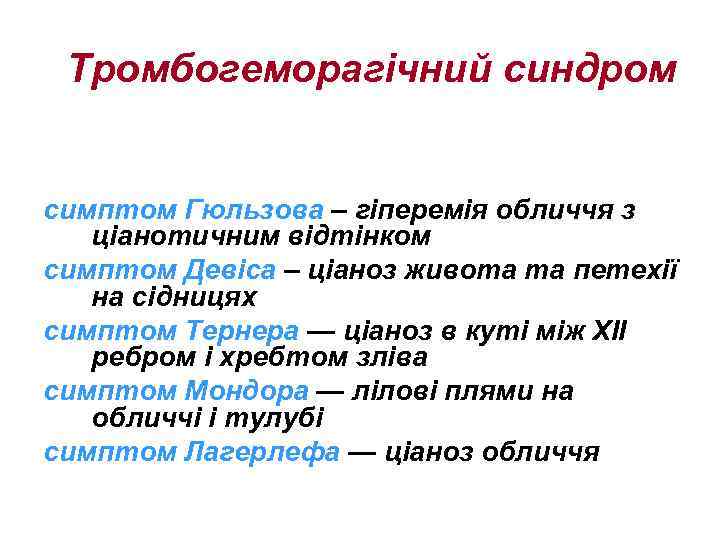

Тромбогеморагічний синдром • кровотечі: носові, шлунково-кишкові, маткові, гемороїдальні • загальна і місцева активація фібринолізу – гіпокоагуляція • місцева активація згортання – гіперкоагуляція (тромбози)

Тромбогеморагічний синдром • кровотечі: носові, шлунково-кишкові, маткові, гемороїдальні • загальна і місцева активація фібринолізу – гіпокоагуляція • місцева активація згортання – гіперкоагуляція (тромбози)

Тромбогеморагічний синдром симптом Гюльзова – гіперемія обличчя з ціанотичним відтінком симптом Девіса – ціаноз живота та петехії на сідницях симптом Тернера — ціаноз в куті між ХII ребром і хребтом зліва симптом Мондора — лілові плями на обличчі і тулубі симптом Лагерлефа — ціаноз обличчя

Тромбогеморагічний синдром симптом Гюльзова – гіперемія обличчя з ціанотичним відтінком симптом Девіса – ціаноз живота та петехії на сідницях симптом Тернера — ціаноз в куті між ХII ребром і хребтом зліва симптом Мондора — лілові плями на обличчі і тулубі симптом Лагерлефа — ціаноз обличчя